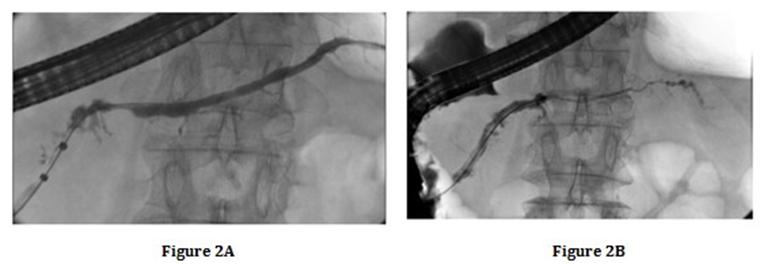

Six months after the initial hospitalization, follow-up MRCP revealed short narrowing of the MPD (length, 5 mm) proximal to the IPMN in the pancreatic body (Figure 1B). A mass was not evident in both CT and MRI. Endoscopic retrograde cholangiography (ERP) showed the short narrowing of the MPD (length, 6 mm) in the pancreatic body (Figure 2A). The diameter of the upstream MPD was 3 mm. A 10-mm diameter cystic lesion communicating with the MPD was detected on ERP. Brush cytology examination was performed at the site of MPD narrowing. However, the cytology specimen showed no malignancy on pathological examination. The serum levels of CEA and CA19-9 were 3.3 U/mL and 10.9 U/mL, respectively. The serum amylase level was 118 U/L. The serum IgG4 level was slightly elevated (109 mg/dL; normal range, 4.8–105 mg/dL), but was lower than the serological criteria (>135 mg/dL) according to the Japanese diagnostic criteria 2011 (JPS2011) [2]. Therefore, AIP could not be diagnosed according to the JPS2011 [2] or the International Consensus Diagnostic Criteria (ICDC) [3], and furthermore, pancreatic cancer associated with IPMN could not be excluded. Therefore, we recommended that the patient undergo surgery, but the patient rejected the recommendation.

Figure 2A-B. Endoscopic retrograde pancreatography showing a remarkable change of MPD; A. Short narrowing of the MPD (length, 6mm) in the pancreatic body after 6 months; B. Segmental narrowing of the MPD after 24 months. |

Quadriphasic CT, performed 24 months after the initial hospitalization, revealed segmental enlargement of the pancreas body and tail with a capsule-like low density rim. Segmental enlargement of the pancreatic parenchyma appeared hypoattenuating compare to normal spleen parenchyma during the pancreatic phase of the dynamic study (Figure 4B). This pancreatic parenchyma became more dense during successive phases of study, and appeared isoattenuating compare to normal spleen parenchyma during portal venous (Figure 4C) and delayed (Figure 4D) phases. Moreover, on MRCP, progression of MPD narrowing was noted (Figure 1D). At that time, the serum IgG4 level was elevated to 163 mg/dL. The serum levels of CEA and CA19-9 were 3.8 U/mL and 13.6 U/ mL, respectively. EUS revealed a segmental enlargement and a capsule-like rim in the pancreas body and tail. In addition, segmental narrowing of MPD was observed on ERP (Figure 2B). Thus, the patient was diagnosed with diffuse type AIP according to the JPS2011 [2] and ICDC [3]. EUS-FNA of the pancreatic body was performed to obtain histopathological evidence of AIP. The obtained tissue showed no malignancy, but lymphoplasmacytic infiltration, storiform fibrosis, obliterative phlebitis, and abundant IgG4-positive plasma cells were not observed. Therefore, it did not meet the histological criteria of JPS2011 and ICDC. In the present case, we did not administer steroid therapy because the patient had no symptoms and was of advanced age. The patient was discharged and followed- up for 6 months after the diagnosis of AIP.

In the present report, narrowing of the MPD was short (length, 6 mm) and the upstream MPD was not dilated (diameter, 3 mm) when narrowing of the MPD was first observed. We primarily suspected the presence of pancreatic cancer at that time. However, after 10 months, narrowing of the MPD progressed (length, 12 mm) and the upstream MPD was found to be dilated (diameter, 5 mm). Therefore, we strongly suspected the presence of pancreatic cancer associated with IPMN; however, no evidence of malignancy was observed by EUS-FNA. After an additional 9 months, MPD narrowing had progressed, and segmental narrowing of the MPD was observed on ERP. Finally, we diagnosed the patient with diffuse type AIP according to the JPS2011 and ICDC. This marked change in the MPD from short focal narrowing to segmental narrowing was indicative of this condition, considering the natural history of AIP.